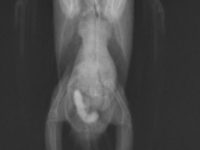

症例紹介 2026年3月30日 ケヅメリクガメの膀胱結石 今回はケヅメリクガメの膀胱結石をご紹介します。 ケヅメリクガメやホシガメは膀胱結石が多くみられます。 原因としては慢性的な脱水や食事の問題、細菌感染などが尿路結石の原因として知られています。 この子も排泄をするときに鳴く […]